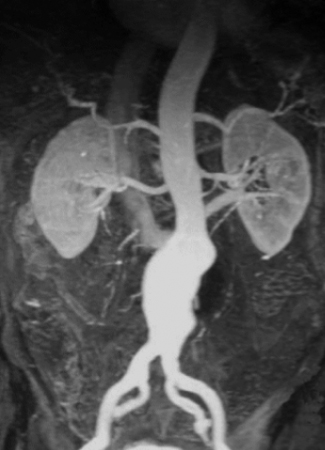

La Ecografía es el método de elección para el diagnóstico inicial, no solo por su amplia disponibilidad sino porque permite rápidamente la realización de mediciones en el plano longitudinal, anteroposterior y transverso (Fig. 26). Está indicada para la realización del screening del aneurisma de aorta abdominal en pacientes mayores de 65 años y con factores de riesgo.

La técnica de evaluación del aneurisma de aorta abdominal incluye mediciones, las cuales deben realizarse desde los bordes externos de la misma. En el plano longitudinal se examina la aorta desde el diafragma hasta la bifurcación ilíaca, y se miden el diámetro anteroposterior y la longitud del aneurisma. En el plano axial se mide el diámetro transverso. Para categorizar el tipo de aneurisma se examina la relación y distancia del aneurisma con respecto a la emergencia de la arteria mesentérica superior, de las renales y de la bifurcación ilíaca. Se examinan las arterias ilíacas y se mide su diámetro para determinar si están comprometidas. Las arterias ilíacas primitivas tienen un diámetro anteroposterior normal de hasta 11 mm (Fig 27).

En cuanto a la Angio Resonancia con gadolinio, permite una óptima visualización de la morfología del aneurisma, sus angulaciones y tortuosidades, así como también identificar bien los vasos renales y viscerales. Es importante mencionar que, a diferencia de la Angio TC, en este caso la Resonancia no utiliza radiaciones ionizantes ni contrastes iodados endovenosos. La desventaja es que no logra una buena definición del diámetro transverso del cuello ni de las arterias ilíacas (Fig. 32).